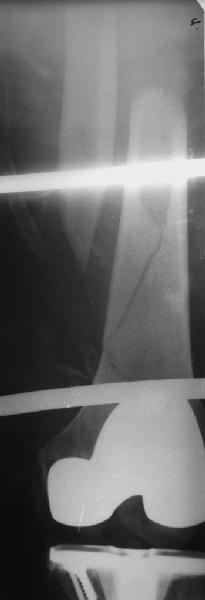

В приложении - недавний перипротезный перелом.

Хотя закрытый остеосинтез блокированным гвоздем выглядит технически проще, особенно при диафизарных переломах. Не говоря о биомеханических преимуществах внутрикостного имплантата, еще меньшей инвазивности, возможности динамизации при проблемах со сращением... Стоимость гвоздей и пластин сопоставимая, на рынке есть масса отечественных предложений.

Представляю вам один из наших недавних случаев выполнения малоинвазивного остеосинтеза бедренной кости обычной пластиной 95 градусов. Длина восстановлена с помощью дистрактора (по сути это основная и б(о)льшая часть репозиции). Произведено два небольших доступа, проведена спица направитель. Рентген-контроль для подтверждения достаточной длины/оси (ЭОП использовался в другой операционной). Создание туннеля обратной стороной фиксатора. Поворот фиксатора, введение клинка по спице. Фиксация проксимального и дистального концов пластины.